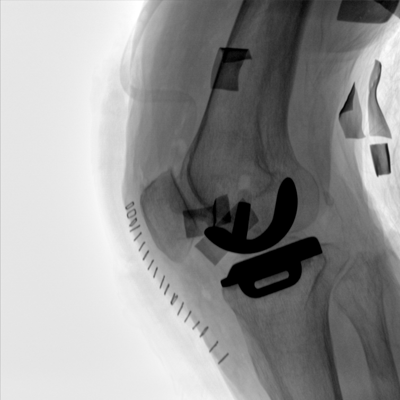

動態(tài)板C形臂 開啟清晰影像新篇章

臨床適用科室:骨科、普通外科、矯形外科、創(chuàng)傷外科、泌尿外科、脊柱外科、疼痛外科、消化科、婦科等科室。

大尺寸動態(tài)平板探測器,高DQE、低噪聲、圖像清晰。采用多分辨率圖像增強(qiáng)處理技術(shù),不同部位不同圖像處理算法,滿足客戶多樣化的需求。

采用智能變頻脈沖透視技術(shù),優(yōu)化圖像質(zhì)量的同時降低輻射劑量,呵護(hù)醫(yī)患健康